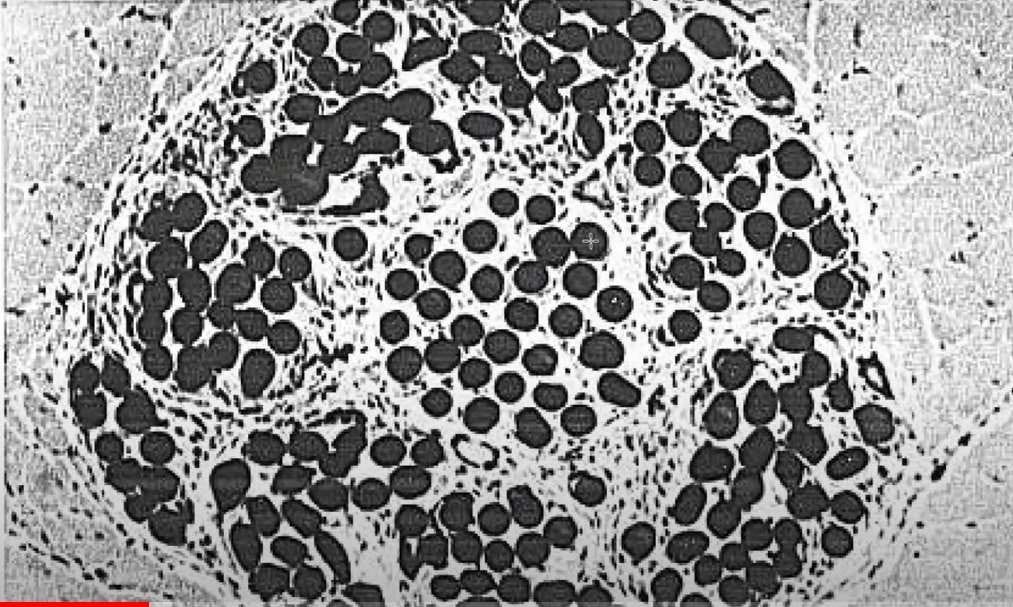

Considera-se a pele o maior órgão do corpo humano, pois envolve todo o organismo externamente. Alguns autores descrevem a pele como sendo constituída por três camadas: epiderme, derme e hipoderme. Outros consideram apenas duas camadas, a epiderme e a derme. A hipoderme, abaixo da derme, possui a função de união e suporte dos órgãos subjacentes. Nela encontram-se vasos sanguíneos, nervos, extremidades sensoriais, glândulas sudoríparas, sebáceas, folículos pilosos e uma camada de tecido adiposo (7).

De acordo com Benedetti (9), a epiderme, sendo a camada mais externa, é formada por camadas estratificadas e queratinizadas. A epiderme possui uma barreira de proteção, o manto hidrolipídico, que contém substâncias oleosas, ceramidas, aminoácidos, água e suor.

O estrato córneo, a camada mais externa da epiderme, é formado por células achatadas e sem núcleo, ligadas por desmossomos. Por muito tempo, foi considerada uma camada de células mortas. Entre o estrato córneo e a camada basal, existem outras três camadas: espinhosa, granulosa e lúcida.

Na camada basal, ou germinativa, as células prismáticas chamadas de queratinócitos realizam mitoses constantes, originando as novas células da pele. Acima delas, localizam-se os melanócitos, que contêm melanina e protegem as células contra a radiação ultravioleta. Além dos melanócitos e queratinócitos, existem as células de Langerhans (resposta imunológica) e as células de Merkel (percepção do toque) (7).

Na derme, encontram-se as células fibroblastos (produção de elastina e colágeno), o sistema imune (macrófagos, linfócitos) e os anexos da pele. Abaixo da derme, localiza-se o Tecido Subcutâneo ou Hipoderme, que protege contra variações de temperatura e choques mecânicos (7).